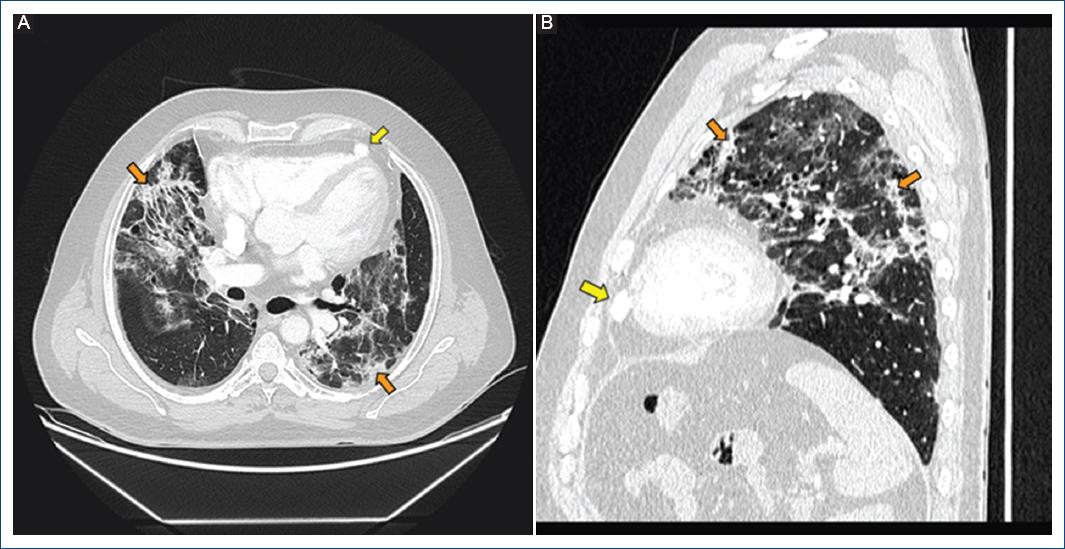

Figura 1 Infiltrados pulmonares en vidrio deslustrado y consolidaciones de distribución periféricas (flecha naranja) en relación con neumonía por COVID-19. Se evidencia una imagen sacular pediculada de 19 × 12 mm en el ápex del ventrículo derecho sugestiva de divertículo (flecha amarilla).

Varón de 56 años con enfisema pulmonar y episodios previos de neumotórax espontáneos secundarios a bullas subpleurales. Acude a nuestro centro por clínica de fiebre 38.5 °C, disnea de reposo y tos seca. En la radiografía de tórax se observa patrón intersticial bilateral, por lo que ingresa con sospecha de neumonía bilateral por COVID-19, posteriormente confirmada con PCR positiva. Se completa el estudio con tomografía computarizada pulmonar (Fig. 1), en la que se objetivan infiltrados pulmonares en vidrio deslustrado y consolidaciones de distribución periféricas en relación con neumonía por COVID-19. Incidentalmente se evidencia una imagen sacular pediculada de 19 × 12 mm en el ápex del ventrículo derecho sugestiva de divertículo. Ante la presencia de disfunción ventricular izquierda en la ecocardiografía, se completa el estudio con tomografía computarizada cardiaca (Fig. 2 A y B), excluyendo cardiopatía isquémica y confirmando el diagnóstico incidental de divertículo apical de ventrículo derecho. Finalmente, se lleva a cabo una resonancia magnética cardiaca (Fig. 2 C y D) para descartar una miocardiopatía, valorando igualmente el divertículo y el comportamiento funcional del flujo a su través mediante técnica 4DFlow (Vid. 1-2) (Fig. 2 D. Respecto a la disfunción ventricular izquierda, se instauró tratamiento farmacológico con un betabloqueante y un inhibidor del sistema renina angiotensina aldosterona, con mejoría de la función ventricular en el seguimiento realizado. Por otro lado, respecto al divertículo, por tratarse de un hallazgo incidental y ante la ausencia de eventos embólicos y taquiarritmias, se adoptó un manejo conservador, sin complicaciones hasta el momento actual.